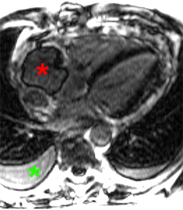

Envahissement tumoral de la paroi latérale du VG avec hypersignal T2 (séquence STIR) et hypersignal post-gadolinium (PSIR) chez un patient de 49 ans aux antécédents de séminome une quinzaine d’année auparavant avec récidive l’année précédente, traitée par chimiothérapie et extension sous forme de nodules pulmonaires et de métastase cérébrale traitée par radiothérapie. La paroi latérale infiltrée est hypokinétique avec FEVG abaissée à 54%.